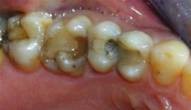

Case 1

missing

Decayed Tooth

After Composite Filling